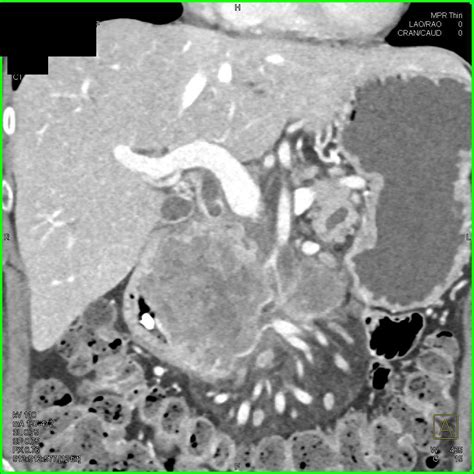

• Contrast-Enhanced CT: This involves injecting a contrast agent to enhance the visibility of the pancreas and surrounding structures. It is particularly useful for detecting small lesions and assessing blood flow.

• Multiphase CT: This technique captures images at different phases of contrast enhancement, providing a comprehensive view of the pancreas and its vasculature.

• 3D Reconstruction: Advanced software can create three-dimensional images of the pancreas, aiding in surgical planning and visualization of complex structures.

These advanced techniques offer a more detailed and accurate assessment of pancreatic conditions, improving diagnostic accuracy and treatment planning.